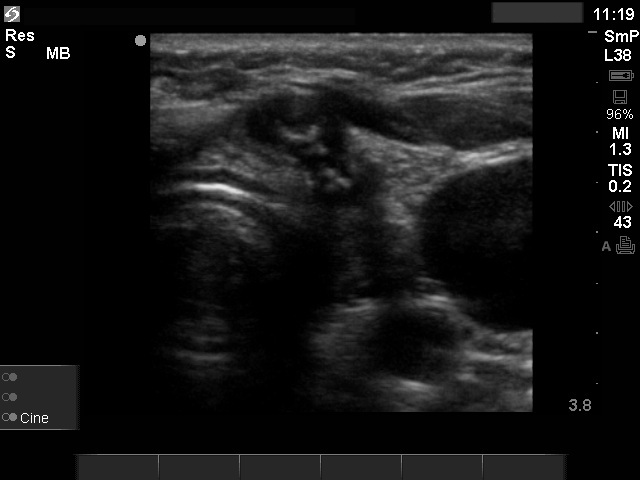

Ultrasonography: there were multiple hypoechogenic lesions containing amorphous hyperechogenic granules in both resected lobes. The lesions were avascular.

Aspiration cytology resulted in benign granulation around surgical thread.